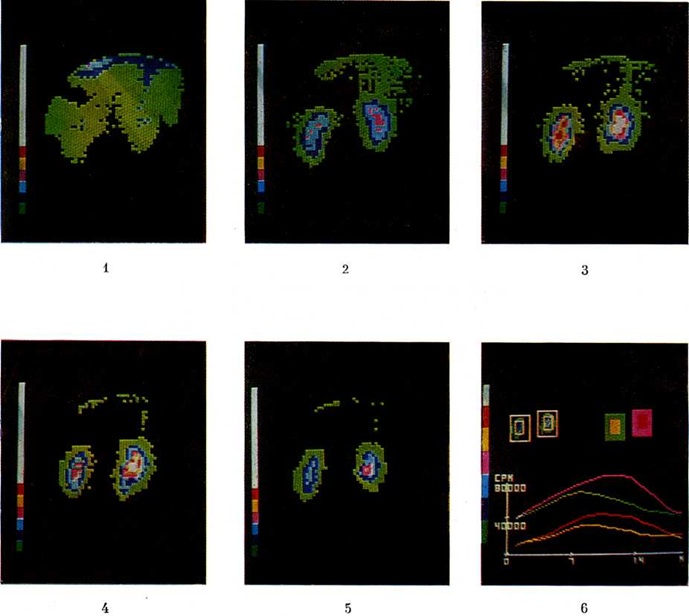

В диагностике Почечнокаменная болезнь для определения функции почек, кровоснабжения и уродинамики используют радиоизотопные методы исследования (цветной рисунок 1—6): ренографию (смотри полный свод знаний: Ренография радиоизотопная) и динамическую сцинтиграфию (смотри полный свод знаний).